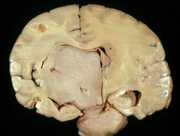

27

B. The most common primarymalignant brain tumor in adults.